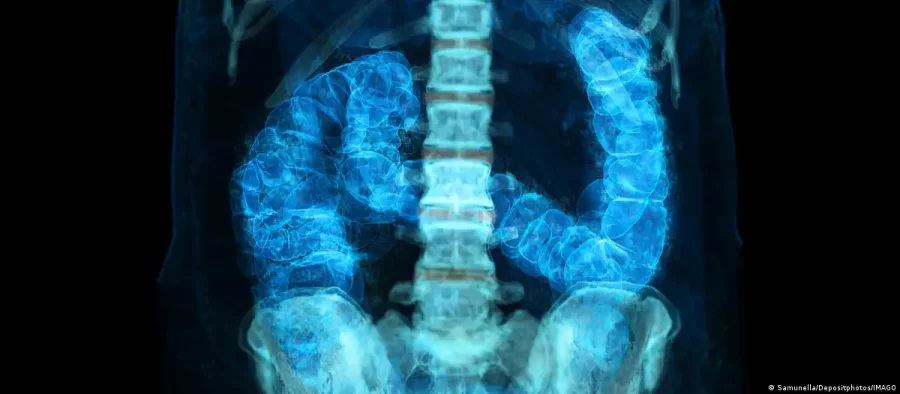

Além disso, o local onde o tumor aparece ao longo do cólon, que tem formato semelhante a um ponto de interrogação, começando de um lado do abdômen, curvando‑se para o outro e terminando no reto, influencia sua agressividade e o tratamento.